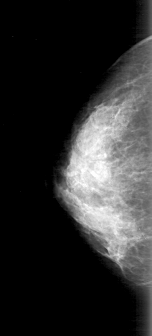

D_4168_1.LEFT_MLO

DATE_OF_STUDY 9 11 1998

PATIENT_AGE 48

DENSITY 3

LEFT_MLO LINES 4951 PIXELS_PER_LINE 2401 BITS_PER_PIXEL 12 RESOLUTION 43.5 OVERLAY